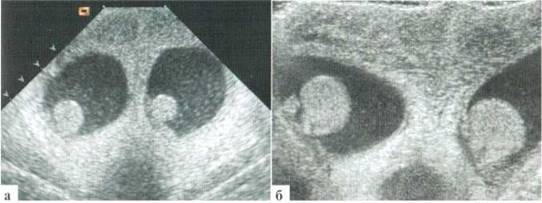

Орхит у детей встречается редко, чаще в подростковом возрасте, но зафиксирован и у новорожденных. Причина заболевания не всегда ясна, клинико-лабораторное подтверждение инфекции мочевыводящих путей, которой отводится известная роль в генезе орхитов и эпидидмитов, имеет место далеко не всегда. Характерны весьма разнообразные изменения структуры яичка в В-режиме: от редко выраженных до практически не дифференцируемых. В большинстве случаев имеет место некоторое увеличение яичка в размерах, преимущественно — в толщину, при этом оно приобретает шаровидную форму. Эхогенность паренхимы может оставаться нормальной, может диффузно понижаться. Всегда имеется значительное усиление сосудистого рисунка в паренхиме яичка. Часто определяется некоторое снижение RI артериального тестикулярного кровотока, но, строго говоря, количественная оценка тестикулярного кровотока при гиперемии яичка у детей с орхитами редко дает принципиально новую информацию для оценки состояния пораженного органа. Часто определяется утолщение оболочек яичка за счет их отека и небольшое количество жидкостного содержимого в оболочках (рис. 2.3.1).

Рис. 2.3.1. Орхит слева у ребенка 11 лет: а, б — правое неизмененное яичко 32x15 мм; в, г — левое яичка увеличено в размерах до 42x26 мм, паренхима гомогенная, без значительных структурных изменений, резко выраженное диффузное усиление сосудистого рисунка

Весьма демонстративным является поперечное сканирование мошонки, когда датчик располагается перпендикулярно ее шву, и в поле сканирования попадают одновременно оба яичка или хотя бы их внутренние фрагменты. Изменение формы яичка и интенсивности интратестикулярного сосудистого рисунка не вызывают сомнения (рис. 2.3.2).

Рис. 2.3.2. Поперечное сканирование по передней поверхности мошонки у ребенка 13 лет с правосторонним орхитом с одновременной визуализацией фрагмента правого (D) и левого (S) яичек